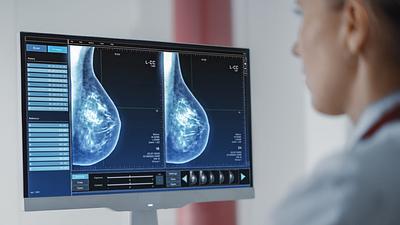

Pesquisa em larga escala aplica IA para detectar câncer de mama

A ferramenta de IA foi aplicada em tempo real e envolvendo um grupo ampliado de pessoas, em vez de ser utilizada posteriormente como vinha sendo feito até agora.

Super Centro usa IA em diagnósticos de câncer de mama

Os laudos dos exames de mamografia realizados no Centro Carioca de Diagnóstico e Tratamento por Imagem (CCDTI) são avaliados e assinados por profissionais médicos capacitados, no entanto, a IA auxilia na identificação de possíveis lesões difíceis de serem vistas.